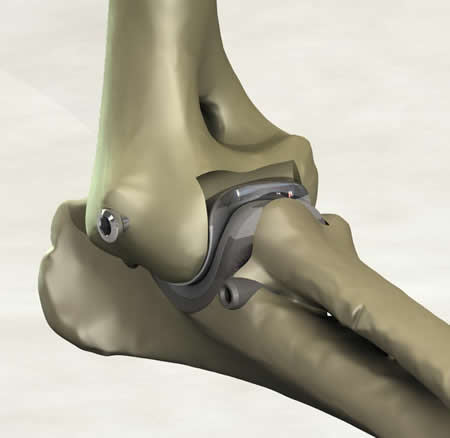

After attending the courses and reviewing the past systems, I had some general concepts. I wanted a medial approach due to lateral luxations seen with other systems. A minimally invasive concept was essential to reduce patient morbidity and decrease the post operative aftercare. After some loose implants with cemented hip systems, I chose a non-cemented system for the elbow.

I remember the day the mill and drill concept was developed and it just felt right. We had attempted bone preparation with saws and spine burrs, and we finally started talking about milling. Custom end mills were developed and the cuts were fast and accurate. We realized that drilling for implant attachment to bone, then milling, would allow preparation of both sides of the joint simultaneously without disarticulation. The collateral ligaments were preserved in their original length with no impingement through the range of motion. The cartridge concept soon followed, and I felt we were on the way. After implanting many cadavers with different SLA prototypes, our tenth prototype felt right in the cadaver. We tested for full range of motion with stability in extension and flexion.

What is novel about the concept?

Simultaneous preparation of both joint surfaces using the axis of rotation as the mill datum has not been done before. The other unique aspect of the patent is inserting both components of an arthroplasty together as a cartridge. These concepts potentially provide for improved alignment of the implants, reduced surgical trauma and reduced surgical time.